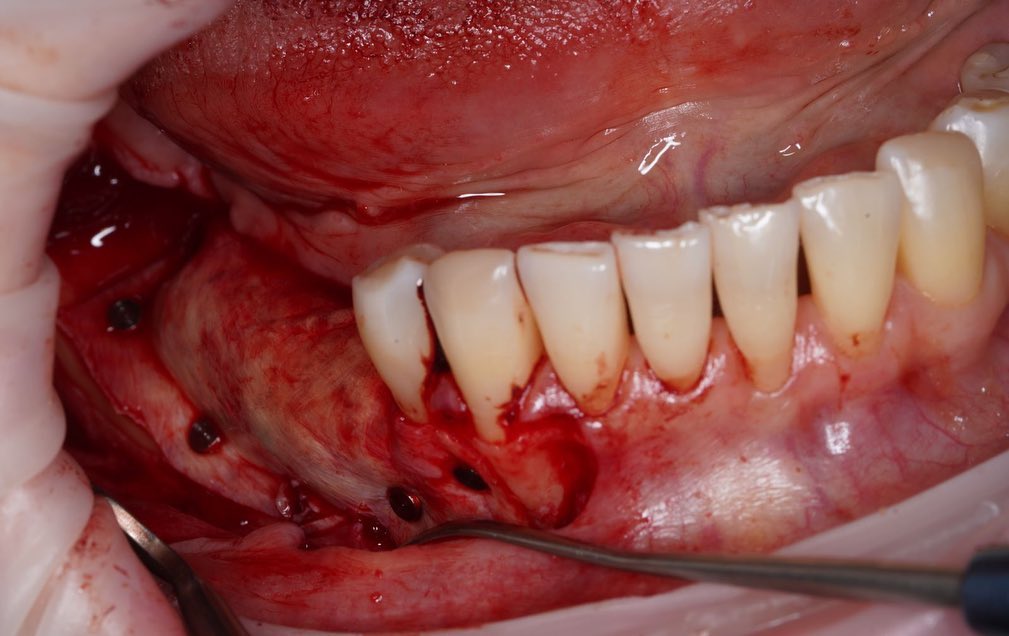

Проведена направленная костная регенерация жевательной группы зубов с использованием костного заменителя и мембраны.

После проведения НКР пациенту назначена имплантация.